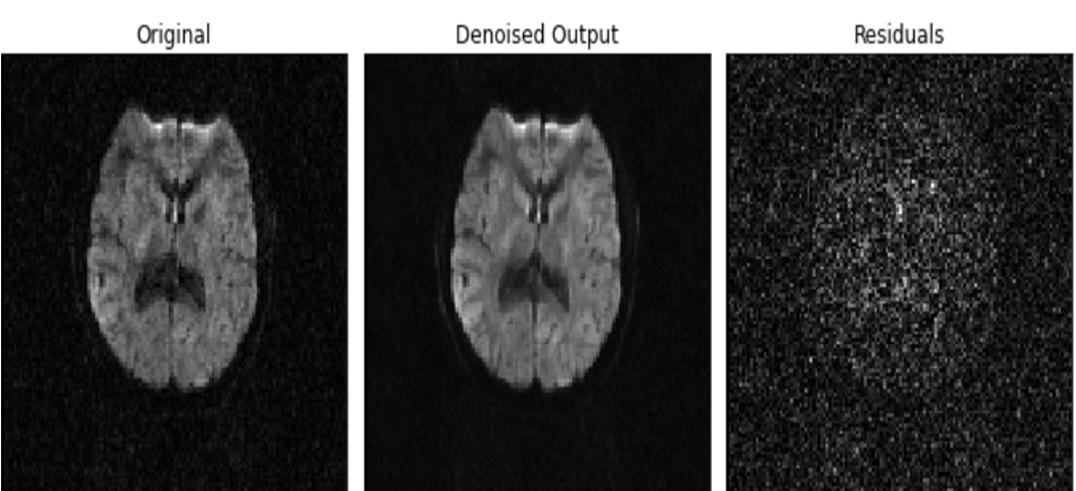

D. Preprocessing

We have also done pre processing for taken data which is called by the name Patch2self which is a self supervised learning method for denoising DWI data, this makes use of the whole volume in order to learn a full rank locally linear denoiser for the volume in question. Utilizing the oversampled q space that the DWI data provides for our benefit. Patch2Self can be implemented at any stage of the pre processing pipeline, as it relies solely on the noise's randomness. it is designed to operate on any sort of diffusion data or body part without requiring a noise calculation or assumptions about the nature of noise (such as its distribution).

Fig. 2 The above figure demonstrates the working of Patch2Self. The idea is to build a new regressor for denoising each 3D volume of the 4D diffusion data

Fig. 3 Denoised Output